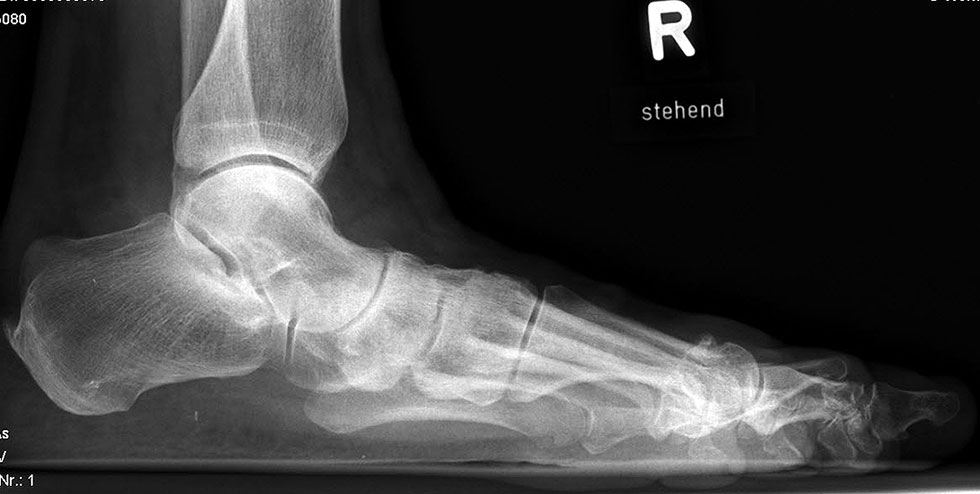

Stehende konventionelle Röntgenbilder eines Fußes mit Planovalgus Deformität Stadium II b dorsoplantar (dp) und seitlich. Auf der dp-Aufnahme zeigt sich die talo-calcaneare Divergenz, der gegenüber dem Kalkaneus nach anterior gleitende Talus und d

Abbildung 5

Stehende Aufnahmen des Fußes dorsoplantar (dp) und seitlich sowie des OSG anteroposterior (ap) sind die Grundlage der konventionellen Röntgendiagnostik (Abb. 5). Ergänzend werden gelegentlich die Rückfuβ-Alignement Aufnahme nach Saltzman 19 und Vergleichsaufnahmen der Gegenseite durchgeführt.

Auf der seitlichen, stehenden Aufnahme des Fußes wird ebenfalls der laterale Talo-Metatarsale I Winkel (Abb. 6 d) gemessen und so das kollabierte mediale Längsgewölbe dokumentiert. Auch hier gilt ein Talo-Metatarsale I Winkel von > 5° (nach plantar konvex) als pathologisch 21. Der Kollaps findet dabei meist im Talonaviculargelenk, seltener in der Naviculocuneiform-Gelenkreihe statt. Instabilität und Arthrose im 1. TMT sollten ausgeschlossen oder bei der Operationsplanung mit einbezogen werden. Weitere wichtige radiologische Messungen zur Beurteilung der Planovalgus-Statik und Progression der Deformität sind der laterale talo-calcaneare Winkel (Abb. 6 e) und der Abstand des Os cuneiforme-Unterrandes zum Untergrund (Abb. 6 f, Cuneiform height, 22. Eine anteriore Translation des Talus auf dem Kalkaneus findet man sowohl auf der ap, als auch auf der seitlichen Aufnahme des Fuβes mit Aufhebung der Cima-Linie.